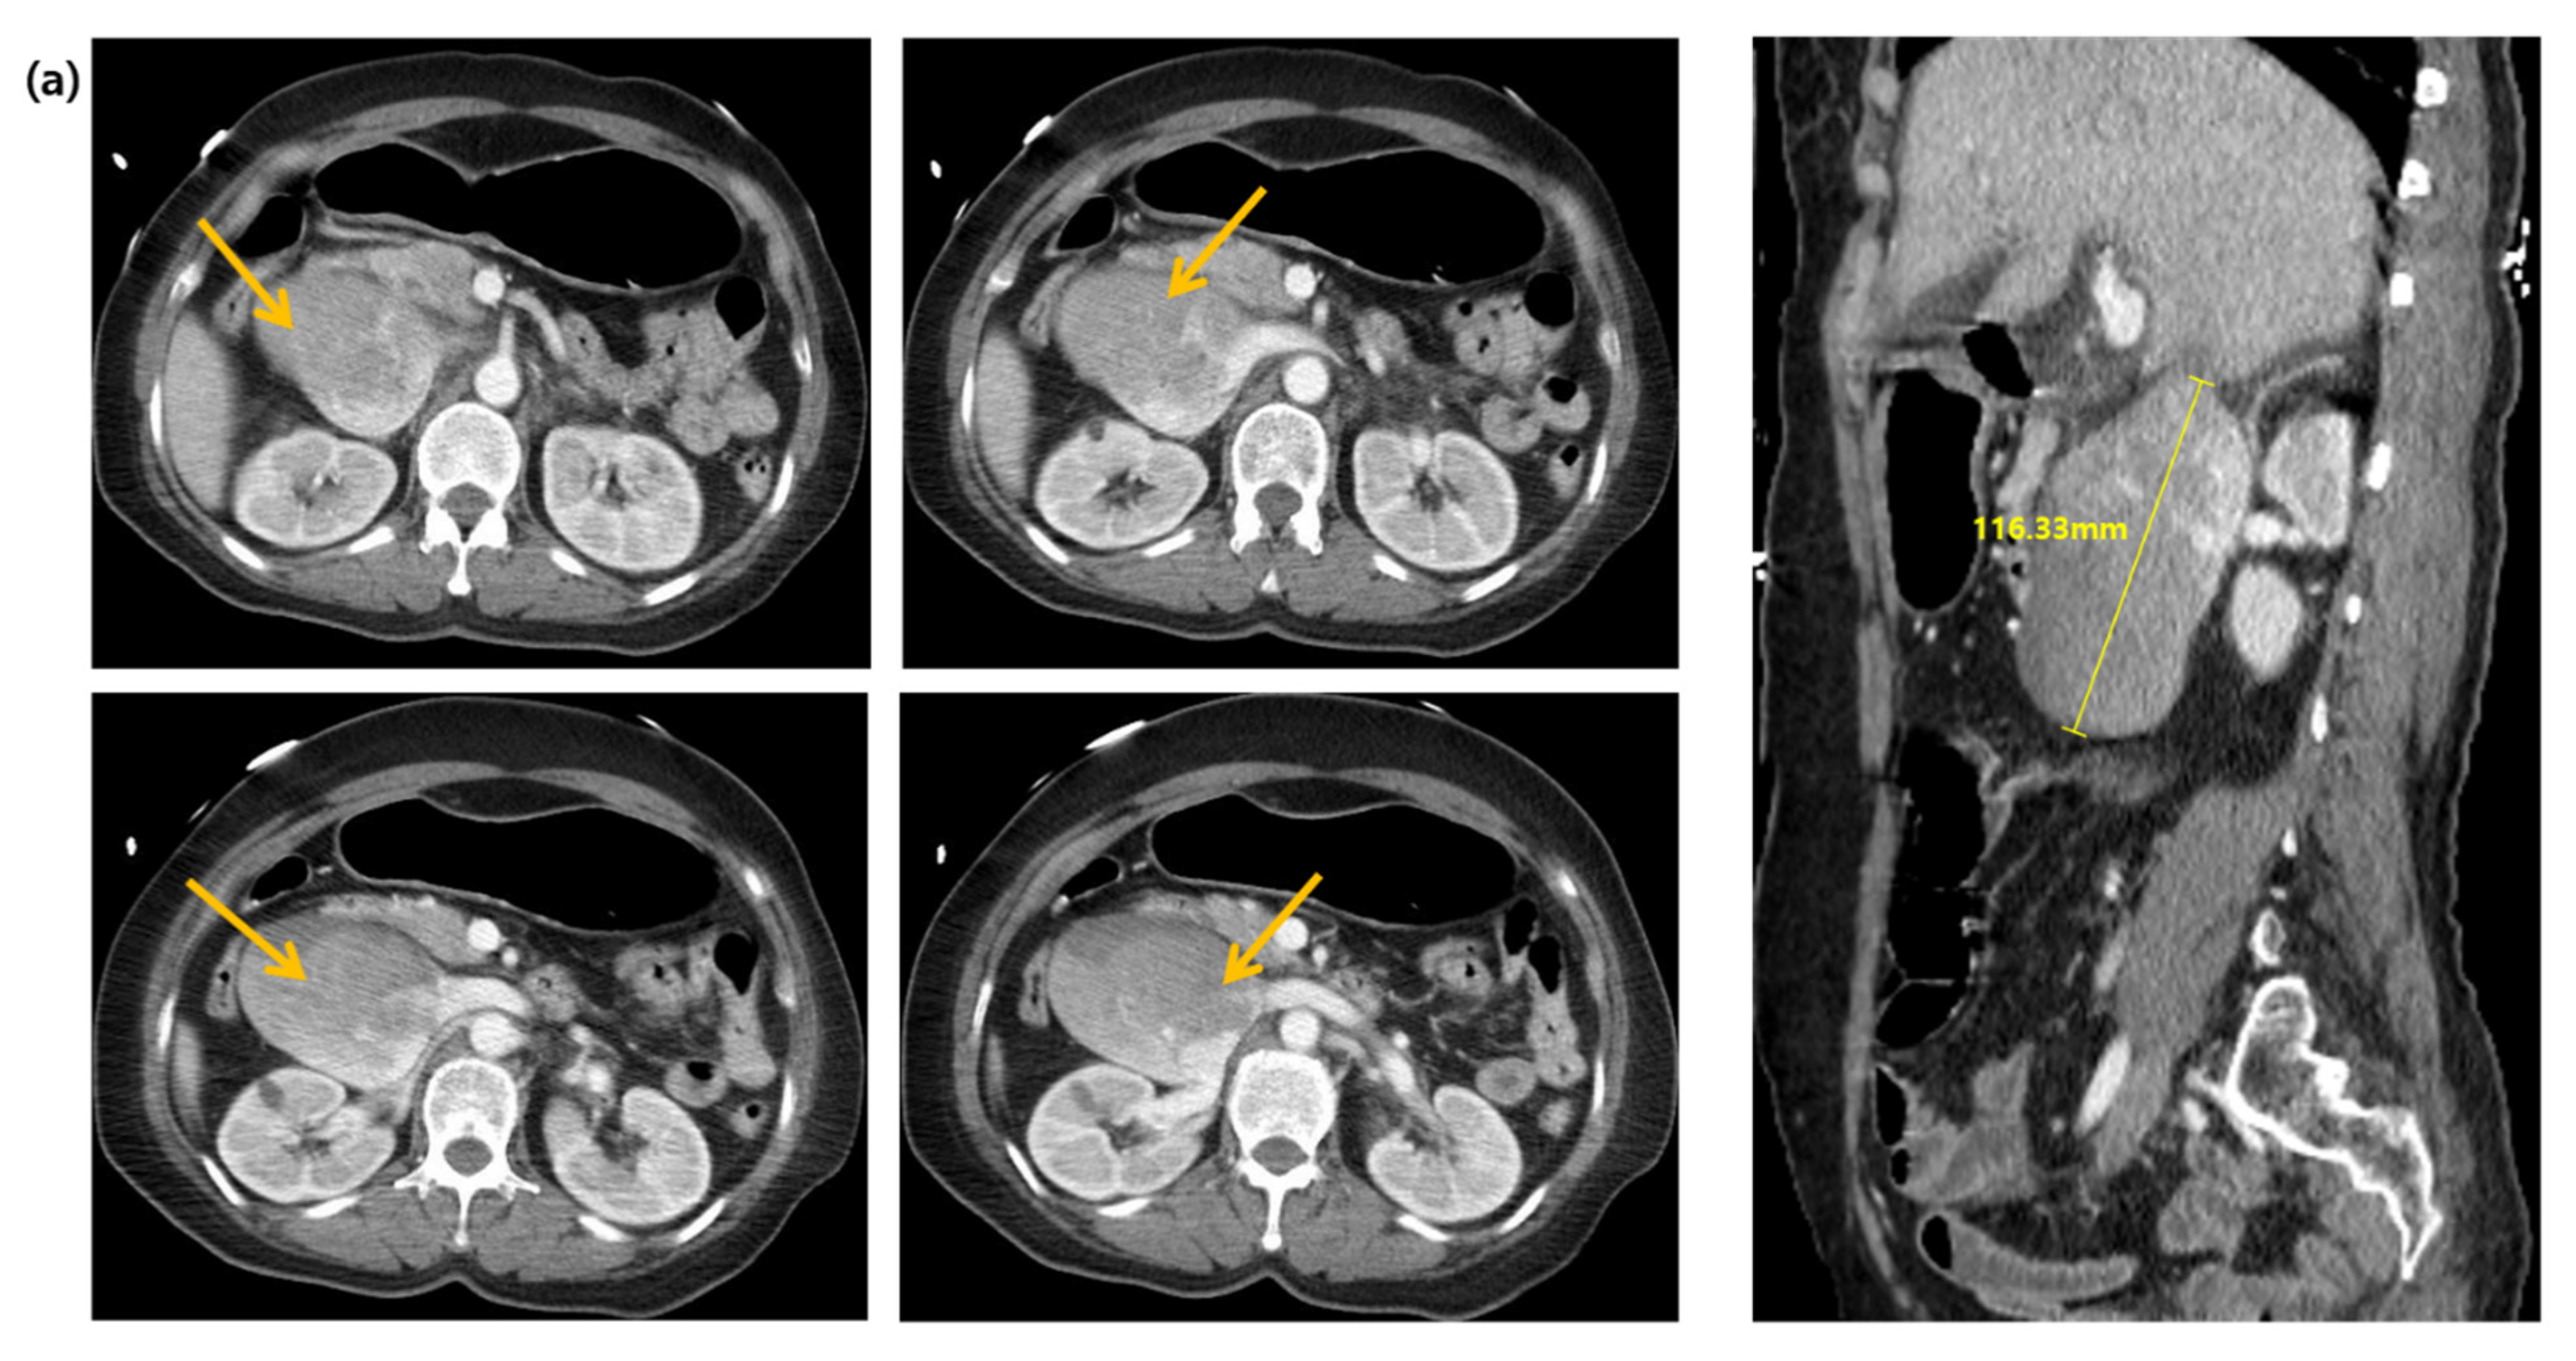

2. Case Presentation